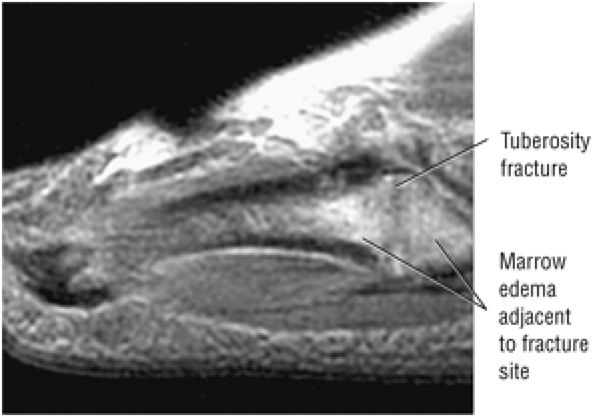

Stage I: Subchondral trabecular compression. Radiograph results are negative, bone scans are posi-tive, and marrow edema is seen on MR imaging (Fig. 5.95).